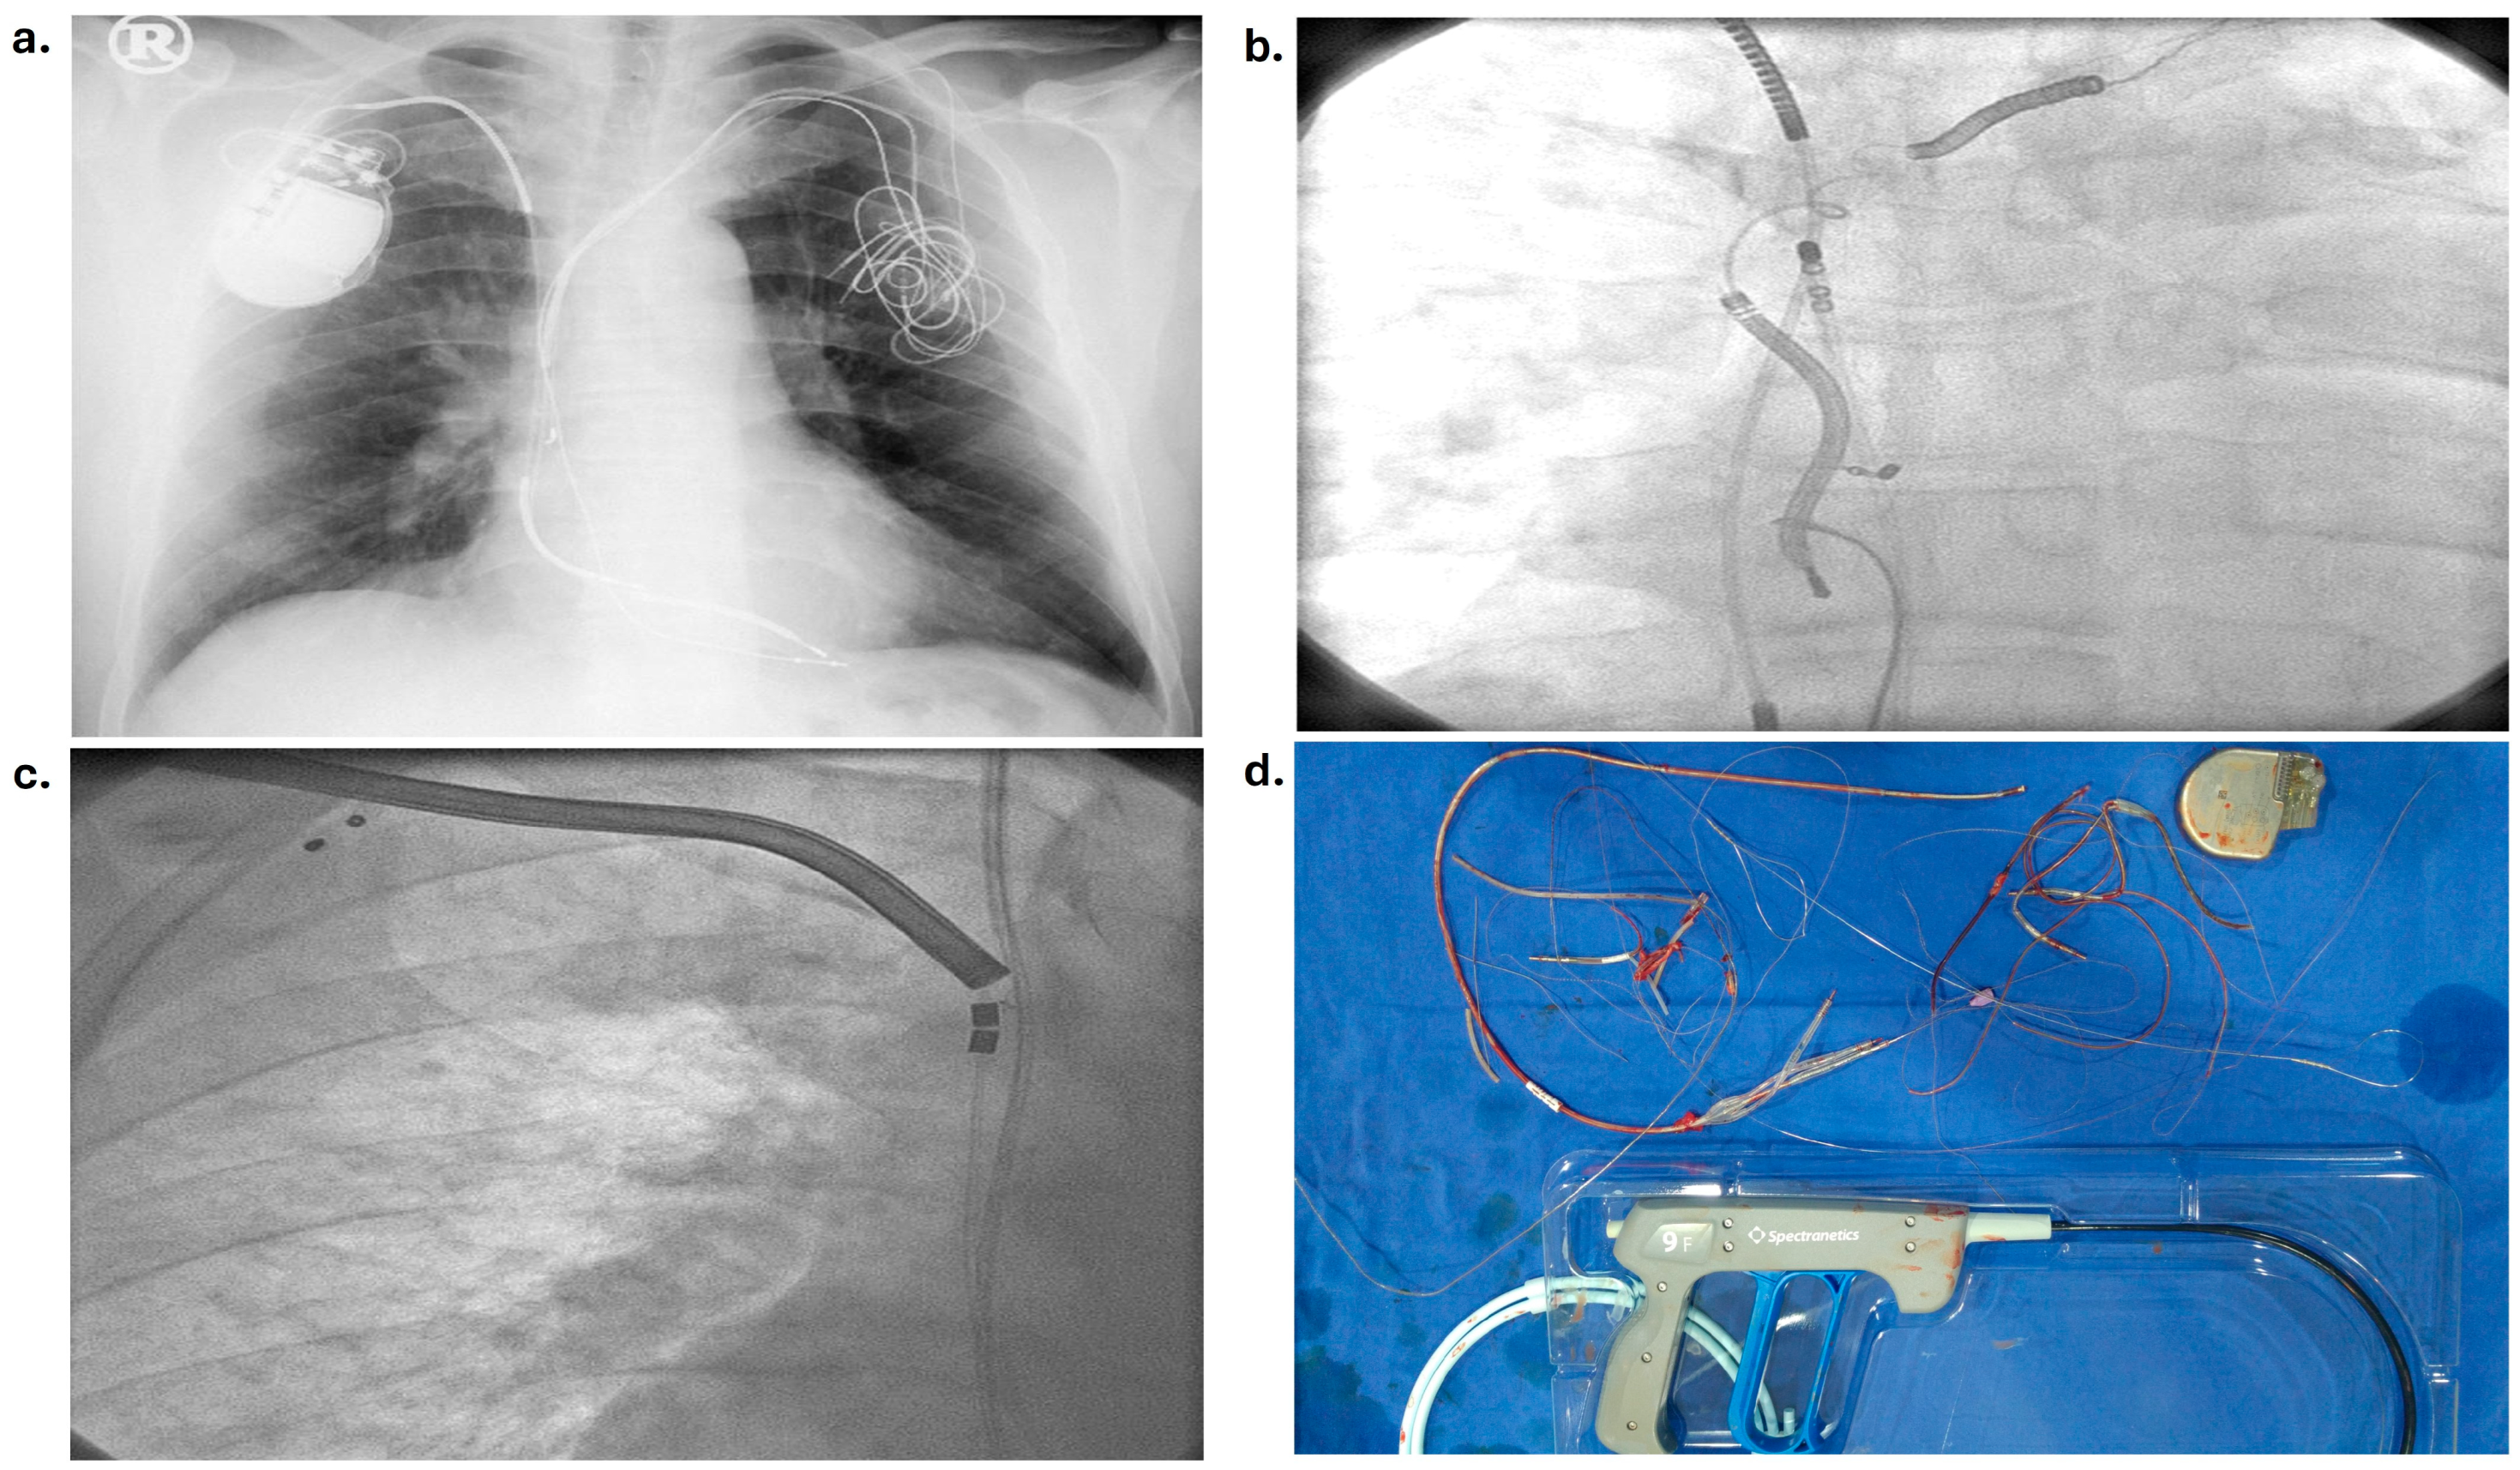

2.2. Lead Extraction Technique

| Extraction technique | n = 93 (%) |

| Simple manual traction method | 79 (85%) |

| Use of extraction system | 5 (5%) |

| Use of snare loop | 9 (10%) |